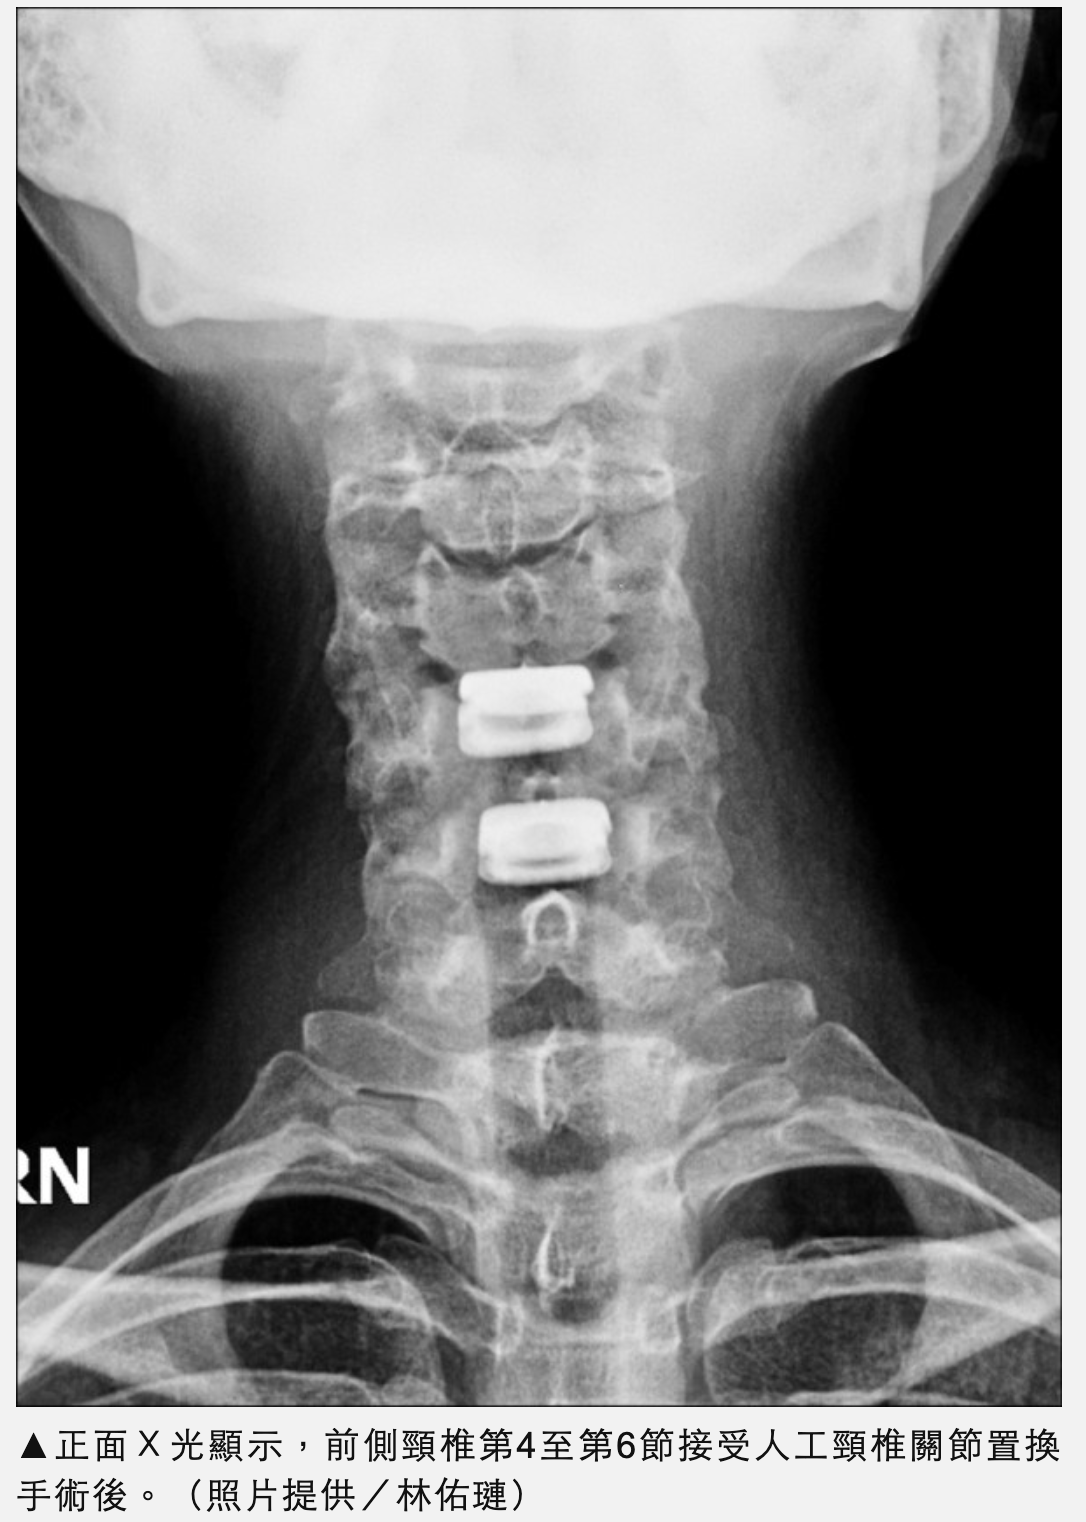

一名36歲台積電工程師因長期於無塵室操作電機配備及電腦,右側持續性的肩膀及右前臂痠麻,更惡化到右手無力。檢查後是頸椎第4節至第6節椎間盤突出造成第4節至第6節右側神經根以及脊隨壓迫。在接受微創頸椎第4節至第6節人工頸椎間盤置換後,術後6小時下床活動,手術後24小時出院,手術後第3天回到無塵室的工作。於手術後3個月在高爾夫球場上揮桿自如。

目前人工頸椎椎間盤有超過30年的發展,美國食品藥物管理局於2007年同意使用在人體上,於近幾年臨床實證手術後的追蹤,在頸椎活動度及鄰近節的退化問題優於傳統前側頸椎融合手術,日本也於2019年開始了人體試驗。由於人工頸椎椎間盤的高額單價,台灣健保署於2021年12月開始有條件地給付頸椎第4節至第6節人工頸椎間盤,一次手術申請一顆為人工頸椎椎間盤置換是將突出椎間盤移除,置換成人工椎間盤,能夠保持椎體間的高度,一併解除壓迫脊神經的椎間盤或骨刺。可動式人工椎間盤提供的活動角度(前後仰,及左右側彎各約8度,左右轉的角度則與健康脊椎相同),除了能夠貼近頸椎自然的活動角度並減緩了手術後鄰近節退化的程度。